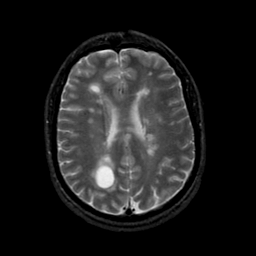

MR Study #21, November 3, 1991 -- Slice #32